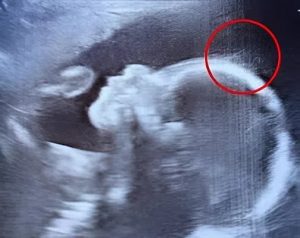

Στην πραγματικότητα, ο υπέρηχος έδειξε λεπτές τούφες να λικνίζονται κάτω από το νερό σαν φύκια.

Η μικρή Ivy γεννήθηκε δύο μήνες αργότερα, με μαλλιά τόσο πυκνά και μακριά όσο ενός δίχρονου. Οι γιατροί και οι νοσοκόμες ισχυρίστηκαν ότι δεν είχαν ξαναδεί κάτι παρόμοιο. Εξήγησαν επίσης στη νέα μητέρα ότι δεν είναι ασυνήθιστο να έχει τρίχες κατά τη γέννηση, καθώς οι τρίχες αρχίζουν να φυτρώνουν ήδη από τις 30 εβδομάδες στη μήτρα. Αξιοσημείωτο είναι ότι τα μαλλιά της Άιβι ήταν ορατά σε όλο το υπερηχογράφημα και ήταν ασυνήθιστα μακριά για νεογέννητο.